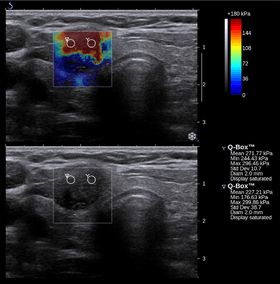

Elastography

Nowadays, the medical imaging modality of elastography can also be used to determine the stiffness of tissues. Manual palpation suffers from several important limitations: it is limited to tissues accessible to the physician's hand, it is distorted by any intervening tissue, and it is qualitative but not quantitative. Elastography is able to overcome many these challenges and improve on the benefits of palpation.

Elastography is a relatively new technology, and entered the clinic primarily in the last decade. The most prominent techniques use ultrasound or magnetic resonance imaging (MRI) to make both the stiffness map and an anatomical image for comparison.